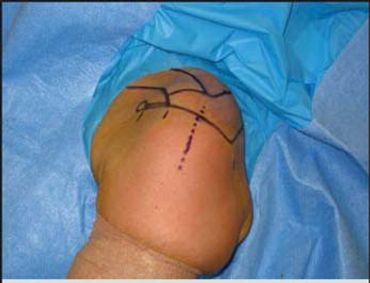

These exercises are designed to progressively strengthen the muscle on the outside of the shoulder (Deltoid) to compensate for tears of the rotator cuff tendons.